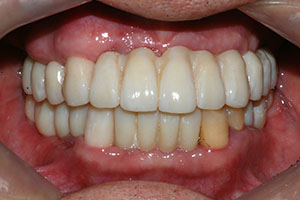

치료증례 전후사진

Before & After